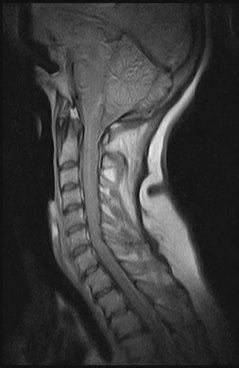

Ressonância Magnética da Coluna em Campinas

RM BrasilCaso esteja à pesquisa de ressonância magnética da coluna em Campinas, venha até a RM Brasil e garanta os melhores valores e condições especiais.Com médicos especialistas, dedicados e empenhados,...

Caso esteja à pesquisa de ressonância magnética da coluna em Campinas, venha até a RM Brasil e garanta os melhores valores e condições especiais.

Com médicos especialistas, dedicados e empenhados, buscamos sempre melhor resolver nossos pacientes.

Caso esteja à pesquisa de ressonância magnética da coluna em Campinas, venha até a RM Brasil e garanta os melhores valores e condições especiais.

Com médicos especialistas, dedicados e empenhados, buscamos sempre melhor solucionar nossos pacientes.